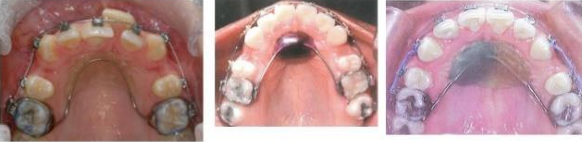

MFD EXAMS /23 6 1234567891011121314151617181920212223 You have 30 min to complete this exam. The timer will start once you begin Attention: Only a few minutes left! Please submit your answers soon. MFD 1 Get a quick sneak peek before the real exam !This trial quiz is designed to show you the question style, difficulty level, and how the options will appear on the platform. 1 / 23 1. What is the lethal dose and toxic dose of fluoride, management? Check 2 / 23 2. What the advantage of silver diamine over other methods and disadvantages ? Check 3 / 23 3. Method of topical fluoride application with concentration ? Check 4 / 23 4. What will happen if left untreated? Check 5 / 23 5. What changes that will happen if the habit stopped? Check 6 / 23 6. Give 3 of your initial stage of treatment? Check 7 / 23 7. What are the causes? Check 8 / 23 8. What is this? Check 9 / 23 9. Then they specified the type of pain and asked about the diagnosis Check 10 / 23 10. What other tests to check vitality of the pulp? Check 11 / 23 11. What are the factors will govern the Rx of Posterior cross bite ? Check 12 / 23 12. What are the factors that govern the treatment of anterior cross bite? Check 13 / 23 13. Name the appliance that you can use to treat this case? Check 14 / 23 14. Name 3 causes? Check 15 / 23 15. Name the most important clinical diagnostic information you need to know. (check RCSI intensive course )? Check 16 / 23 16. What do you see? Check 17 / 23 17. What is your treatment? Check 18 / 23 18. Name the investigations needed? Check 19 / 23 19. causes for gingival enlargement ? Check 20 / 23 20. What is the common side effect of this drug? Check 21 / 23 21. Name the drug that he may take to treat this condition? Check 22 / 23 22. The patient may have what? Check 23 / 23 23. What is this clinical condition? Check /31 2 12345678910111213141516171819202122232425262728293031 You have 30 min to complete this exam. The timer will start once you begin Attention: Only a few minutes left! Please submit your answers soon. MFD 2 Get a quick sneak peek before the real exam !This trial quiz is designed to show you the question style, difficulty level, and how the options will appear on the platform. 1 / 31 1. Mention 2 fixed space maintainers and 2 removable space maintainers other from mentioned : Check 2 / 31 2. Other space maintenance used for child lost primary second molar E before the eruption of the permanent molars ? Check 3 / 31 3. What are the difference between nance appliance and Transpalatal arch Check 4 / 31 4. What material used to attach band? Check 5 / 31 5. What instruction you give to patient? Check 6 / 31 6. Name other fixed space maintainer used in upper jaw and mechanism of their action? Check 7 / 31 7. What component of this appliance? Check 8 / 31 8. What is this appliance , for what its used ? Check 9 / 31 9. Treatment? Check 10 / 31 10. Define Abrasion and Erosion? Check 11 / 31 11. What does this picture show? Check 12 / 31 12. what investigations you can do ? Check 13 / 31 13. Drugs can lead to lichenoid reaction Check 14 / 31 14. What extra oral features in “ Lichenoid reaction )? Check 15 / 31 15. What microscopical features of it ( licheonoid reaction )? Check 16 / 31 16. Definitive diagnosis ? Check 17 / 31 17. Mention type of suggested biopsy ? Check 18 / 31 18. Mention 4 differential diagnosis ? Check 19 / 31 19. Mention 4 questions you will ask the patient ? Check 20 / 31 20. Give 4 intraoral decription of what you see ? Check 21 / 31 21. What the other surgery can be performed to make prothesis? Check 22 / 31 22. Can this tooth stand with fixed prothesis? (in the opg )à taken from Malek file ? Check 23 / 31 23. Radiograph of missing multiple teeth consider it according to Antes law? ON which tooth you will make Abutment ? Check 24 / 31 24. What is Antes law? Check 25 / 31 25. What is best one to use as abutment in fixed prosthesis A or B? Check 26 / 31 26. What relevance of this picture? Check 27 / 31 27. What’s complication of doing surgery in this area floor of mouth? Check 28 / 31 28. Other 2 radiograph needed in diagnosis? Check 29 / 31 29. Give 4 differential diagnosis? Check 30 / 31 30. What can you see ? Check 31 / 31 31. What is the name of radiograph? Check Your score is /30 1 123456789101112131415161718192021222324252627282930 You have 30 min to complete this exam. The timer will start once you begin Attention: Only a few minutes left! Please submit your answers soon. MFD 3 Get a quick sneak peek before the real exam !This trial quiz is designed to show you the question style, difficulty level, and how the options will appear on the platform. 1 / 30 1. Treatment? Check 2 / 30 2. Histopathology? Check 3 / 30 3. Differential diagnosis Check 4 / 30 4. Clinical features’? Check 5 / 30 5. Patient said, this lesion is very frequent, why? Check 6 / 30 6. What are the causes for ulcers? Check 7 / 30 7. Patient have other signs like uveitis ,Genital ulcerations which syndrome he had ? Check 8 / 30 8. Name of the lesion ? Check 9 / 30 9. Mention some TMJ movement ? Check 10 / 30 10. Blood supply ? Check 11 / 30 11. Nerve supply ? Check 12 / 30 12. Which muscles close? Check 13 / 30 13. Action of open and open wide? Check 14 / 30 14. Why it’s Atypical joint ? Check 15 / 30 15. Name of the ligaments ? Check 16 / 30 16. What would be your management? Check 17 / 30 17. Bacteria involved Check 18 / 30 18. Which type of Periodontitis? Check 19 / 30 19. Treatment? Check 20 / 30 20. Histopathology? Check 21 / 30 21. Differential diagnosis? Check 22 / 30 22. Clinical features? Check 23 / 30 23. What are the time frames for making a complaint? Check 24 / 30 24. What are the 3 points related to negligence? Check 25 / 30 25. Who is allowed access to the patient records? Check 26 / 30 26. How to differentiate if it is upper or lower motor neuron lesion? Check 27 / 30 27. Management? Check 28 / 30 28. What are the causes? Check 29 / 30 29. What should you advise the patient to do? Check 30 / 30 30. What is this lesion? Check Your score is /24 1 123456789101112131415161718192021222324 You have 30 min to complete this exam. The timer will start once you begin Attention: Only a few minutes left! Please submit your answers soon. MFD 4 Get a quick sneak peek before the real exam !This trial quiz is designed to show you the question style, difficulty level, and how the options will appear on the platform. 1 / 24 1. What does MRONJ stands for? Check 2 / 24 2. Give definition for MRONJ Check 3 / 24 3. For what medical problems these medications are used? Check 4 / 24 4. Stages of MRONJ 3 Check 5 / 24 5. What’s this appliance? Check 6 / 24 6. At what age is it used? Check 7 / 24 7. What type of malocclusion is it used to treat? Check 8 / 24 8. What changes will produce? (4 options) Check 9 / 24 9. Disadvantages? Check 10 / 24 10. Why is it flabby tissue? Check 11 / 24 11. what is this condition called? Check 12 / 24 12. Causes ? Check 13 / 24 13. Clinical Features ? Check 14 / 24 14. How to avoid it ? Check 15 / 24 15. Management? Check 16 / 24 16. Ideal post length and width Check 17 / 24 17. Definition of Ferrule it’s the Check 18 / 24 18. What is the importance of the ferrule effect ? Check 19 / 24 19. Describe the radiolucency? Check 20 / 24 20. Give 6 differential diagnosis? Check 21 / 24 21. Give 5 radiographical features? Check 22 / 24 22. What is the difference between incisional and excisional biopsy? Check 23 / 24 23. What other 2 plain radiographs we can we can take? Check 24 / 24 24. ALARA? Check Your score is /22 1 12345678910111213141516171819202122 You have 30 min to complete this exam. The timer will start once you begin Attention: Only a few minutes left! Please submit your answers soon. MFD 5 Get a quick sneak peek before the real exam !This trial quiz is designed to show you the question style, difficulty level, and how the options will appear on the platform. 1 / 22 1. . Types of external root resorption? Check 2 / 22 2. The cause of root resorption in the pic? Check 3 / 22 3. How you will treat it? Check 4 / 22 4. What is this probe? Check 5 / 22 5. What is the mark a ? Check 6 / 22 6. What is the mark b ? Check 7 / 22 7. What is the score from the given reading? Check 8 / 22 8. What is the treatment need of the patient according to the score? Check 9 / 22 9. What is the differential diagnosis ? Check 10 / 22 10. Four clinical features of the lesion? Check 11 / 22 11. Treatment ? Check 12 / 22 12. Describe what do you see? Check 13 / 22 13. Causes for it ? Check 14 / 22 14. Treatment ? Check 15 / 22 15. Picture of patient with Anaphylaxis…after taking Check 16 / 22 16. What is diagnosis? - Check 17 / 22 17. What a the signs of Anaphyalxis reactions ? Check 18 / 22 18. What first line of treatment? Dose? Route of Adminstration? Check 19 / 22 19. Other drug used? Check 20 / 22 20. What are expected complications if not treated ? Check 21 / 22 21. What precautions should be made to prevent anaphylaxis reaction ? - Check 22 / 22 22. Name 10 drug in emergency used with their route of Administration and their condition they use in? Check Your score is /36 1 123456789101112131415161718192021222324252627282930313233343536 You have 30 min to complete this exam. The timer will start once you begin Attention: Only a few minutes left! Please submit your answers soon. MFD 6 Get a quick sneak peek before the real exam !This trial quiz is designed to show you the question style, difficulty level, and how the options will appear on the platform. 1 / 36 1. . What are cases that you have to extract the primary tooth? Check 2 / 36 2. D. What are the indications for extraction? Check 3 / 36 3. What are your treatment options? Check 4 / 36 4. Investigations? Check 5 / 36 5. Type of trauma? Check 6 / 36 6. Patient diagnosed with sjorgen syndrome Histology ? - Check 7 / 36 7. Patient diagnosed with sjorgen syndrome Mention four blood investigations ? Check 8 / 36 8. Patient diagnosed with sjorgen syndrome Mention two sites where can we take the biopsy Check 9 / 36 9. Patient diagnosed with sjorgen syndrome How can you differentiate between primary and secondary ? Check 10 / 36 10. Gingival inflammation present in which syndrome Check 11 / 36 11. What is the treatment? Check 12 / 36 12. mention another connective tissue disease that can lead to lesions “ intraorally “ similar to the Lichen planus ? Check 13 / 36 13. what serious complication can arise from Erosive lichen planus ? Check 14 / 36 14. If it was atrophic lesion what histology might be seen ? Check 15 / 36 15. List the histological features of lichen planus ? Check 16 / 36 16. Lichen planus what dose it affect? Check 17 / 36 17. Age group commonly affected ? -ref SAQ Check 18 / 36 18. What are the clinical presentation ‘ types of lichen planus ‘ Check 19 / 36 19. What might you see in patient’s body that has a relation to this lesion? Check 20 / 36 20. What are the differential diagnoses? Check 21 / 36 21. Factors for platelet adhesion? Check 22 / 36 22. What can you see? Check 23 / 36 23. Other 2 process of hemostasis? Check 24 / 36 24. Two diseases in which they increase ? Check 25 / 36 25. Two diseases in which they decrease? Check 26 / 36 26. Medical term when they decrease? And if they increased Check 27 / 36 27. Function Check 28 / 36 28. Life span ? Check 29 / 36 29. From where they arise? Check 30 / 36 30. Normal number? Check 31 / 36 31. What are the function of the guiding plane ? Check 32 / 36 32. The success rate ? Check 33 / 36 33. Mention single extra preparation requirement for Resin bonded bridge in posterior teeth ? Check 34 / 36 34. Mention 5 preparation features of it? Check 35 / 36 35. Give two advantages of it ? Check 36 / 36 36. What’s the name of this prosthesis? Check Your score is /23 1 1234567891011121314151617181920212223 You have 30 min to complete this exam. The timer will start once you begin Attention: Only a few minutes left! Please submit your answers soon. MFD 7 Get a quick sneak peek before the real exam !This trial quiz is designed to show you the question style, difficulty level, and how the options will appear on the platform. 1 / 23 1. If the same scenario but the tooth is subluxated. What is the management? Check 2 / 23 2. Aim of this procedure Check 3 / 23 3. Steps to do this procedure? Check 4 / 23 4. Management? How to asses the vitality of the tooth Check 5 / 23 5. Mention factors that can affect the treatment plan ? Check 6 / 23 6. Identify the Kenneyd’s classification Check 7 / 23 7. Name its parts? Check 8 / 23 8. Uses of Surveyor Check 9 / 23 9. What is this ? Check 10 / 23 10. Criteria for hand piece sterilization Check 11 / 23 11. steps for wrapped instrument sterilization process ( ref : sterilization in SDCEP)? Check 12 / 23 12. What is the difference between sterilization and decontamination? Check 13 / 23 13. Optimal temperature & pressure & time for autoclave? Check 14 / 23 14. Difference between vacuum and non-vacuum autoclave in mechanism? Check 15 / 23 15. Optimum temperature? Check 16 / 23 16. Advantage of vaccum over non vaccum? Check 17 / 23 17. What is the significance of forehead wrinkling? Check 18 / 23 18. What is Ramsy haunt syndrome ? Rx ? and is it LMN or UMN ? Check 19 / 23 19. Enumerate 3 extracranial and intracranial causes for this ? Check 20 / 23 20. What are the branches of facial nerve? Check 21 / 23 21. Why do we suture the eye in a patient with Facial Palsy? Check 22 / 23 22. Differentiate between Upper and Lower Motor Neuron lesions? Check 23 / 23 23. What is shown in photograph? Check Your score is /27 0 123456789101112131415161718192021222324252627 You have 30 min to complete this exam. The timer will start once you begin Attention: Only a few minutes left! Please submit your answers soon. MFD 8 Get a quick sneak peek before the real exam !This trial quiz is designed to show you the question style, difficulty level, and how the options will appear on the platform. 1 / 27 1. Mention 4 diseases you would see in HIV Patients? Check 2 / 27 2. Give 2 differential diagnosis for this lesion? Check 3 / 27 3. Describe the lesion shown in Photograph B? Check 4 / 27 4. What is your diagnosis ? Check 5 / 27 5. Describe the lesion shown in Photograph A? Check 6 / 27 6. Disadvantages of gold ? Check 7 / 27 7. Ideal cement for All Porcelain? Check 8 / 27 8. Which cement would u use for high caries risk patient? Check 9 / 27 9. How much would you prepare for functional and non-functional cusps in Gold Crown? Check 10 / 27 10. what crown would you go for in bruxism patients out of these 3? Check 11 / 27 11. Name the 3 restorations? Check 12 / 27 12. After administering Local Anesthesia and deciding the choice of biopsy. What should be done before biopsying the lesion? Check 13 / 27 13. Name 2 systemic steroids with dosage you would recommend for this patient? Check 14 / 27 14. Name 2 topical steroids with dosage you would recommend for this patient? Check 15 / 27 15. What is your diagnosis? Check 16 / 27 16. Describe the lesion shown in photograph? Check 17 / 27 17. Name 5 options to increase retention and stability in class l Check 18 / 27 18. E. What is the function of the RPI system ? Check 19 / 27 19. What are the 2 disadvantages of the 2 restorations you mentioned? Check 20 / 27 20. What materials are your 2 restorations made of? Check 21 / 27 21. Other than implants what restoration would you place in this patient? Check 22 / 27 22. Which Kennedy’s classification is this? Check 23 / 27 23. Describe your management? Check 24 / 27 24. What may be the patient complaint? Check 25 / 27 25. What are the causes of this? Check 26 / 27 26. Describe what you see in the photograph? Check 27 / 27 27. which 4 examinations would you undertake? Check Your score is /31 0 12345678910111213141516171819202122232425262728293031 You have 30 min to complete this exam. The timer will start once you begin Attention: Only a few minutes left! Please submit your answers soon. MFD 9 Get a quick sneak peek before the real exam !This trial quiz is designed to show you the question style, difficulty level, and how the options will appear on the platform. 1 / 31 1. Describe what you see in the photograph? Check 2 / 31 2. Three other features of this syndrome ? Check 3 / 31 3. What is the medical condition associated with it “? Multiple OKC? Check 4 / 31 4. Where expansion occurs in the OKC ? Check 5 / 31 5. From which cells this lesion arises from? Check 6 / 31 6. What is your diagnosis? Check 7 / 31 7. What is the histopathology of the lesion shown in Histology slide? Check 8 / 31 8. Give 4 differential diagnosis? Check 9 / 31 9. What is the consequence of premature loss of deciduous teeth? Check 10 / 31 10. Identify those appliances and mention one use for each and mode of action? Check 11 / 31 11. What component of appliance no. 3 ? Check 12 / 31 12. How to overcome open bite disadvantage ? Check 13 / 31 13. What are Disadvantages of this appliance ? Check 14 / 31 14. What Ceph changes are expected while using this appliance ? Check 15 / 31 15. What is the construction of Twin Block Appliance? Check 16 / 31 16. What skeletal and dental changes are expected while using this appliance ? Check 17 / 31 17. What is the ideal age to treat this condition >? Check 18 / 31 18. Indications of the Twin Block Appliance? Two Check 19 / 31 19. Name the Appliance used to correct this? Check 20 / 31 20. What is the treatment? Check 21 / 31 21. How to prevent it Check 22 / 31 22. Mention three mechanisms of action of Fluoride? Check 23 / 31 23. What is the disease caused by excess Fluoride? Check 24 / 31 24. What are the risk factors associated with this patient? Check 25 / 31 25. Name the principal organism causing this? Check 26 / 31 26. what are the principles of the access cavity Check 27 / 31 27. What is your diagnosis? Check 28 / 31 28. What are principles of cavity preparation? Check 29 / 31 29. What is your Periapical diagnosis? Check 30 / 31 30. What is your Pulpal diagnosis? Check 31 / 31 31. Which test would you undertake? Check Your score is /21 0 123456789101112131415161718192021 You have 30 min to complete this exam. The timer will start once you begin Attention: Only a few minutes left! Please submit your answers soon. MFD 10 Get a quick sneak peek before the real exam !This trial quiz is designed to show you the question style, difficulty level, and how the options will appear on the platform. 1 / 21 1. Patient is 20 years old Mention two treatment options for this case ? Check 2 / 21 2. Patient is 20 years old What is the long term risk for not treating this case ? Check 3 / 21 3. Name of this appliance in the next picture? Check 4 / 21 4. What is the wire used ? Check 5 / 21 5. For which orthodontic cases this appliance is necessary ? Check 6 / 21 6. Why we use retainer ? Check 7 / 21 7. Describe what you see ? Check 8 / 21 8. Differential diagnosis:- Check 9 / 21 9. Name of those muscles ? Check 10 / 21 10. Name the Extrinsic muscles of the tongue? Check 11 / 21 11. . Which nerves innervate the Extrinsic muscles of the tongue?. Check 12 / 21 12. What is the somatic innervation of anterior 2/3 of tongue? Check 13 / 21 13. Which nerve supplies the posterior 1/3 of tongue?. Check 14 / 21 14. From which Pharyngeal arch posterior 1/3 derived from? Check 15 / 21 15. Mention the intrinsic muscle of the tongue ? Check 16 / 21 16. What is the name of this condition ? name the lesion on the skin ? Check 17 / 21 17. Mention 3 drugs that causing it ? Check 18 / 21 18. 2 infections associated with it Check 19 / 21 19. Mention 2 immediate treatment ? Check 20 / 21 20. Why this condition can be fatal ? Check 21 / 21 21. Which test would you undertake? Check Your score is